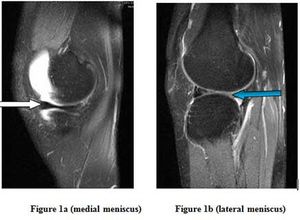

Case History: 26-year-old male with complaints of pain and swelling in left knee joint, had sustained knee injury from falling from a bicycle one month prior.